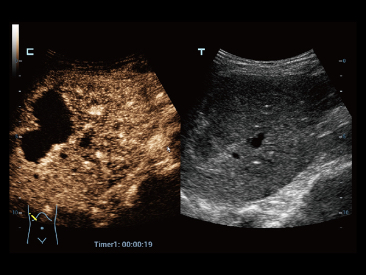

Oprócz uzyskiwania jako?ci obrazu typowego dla aparatów klasy premium, Resona 7 rozszerza mo?liwo?ci klinicznych badań USG dzi?ki rewolucyjnej funkcji V Flow, s?u??cej do oceny hemodynamiki naczyń, a tak?e najlepszej na rynku funkcji inteligentnego, automatycznego uzyskiwania p?aszczyzny na podstawie zestawów danych obj?to?ciowych 3D, umo?liwiaj?cej diagnozowanie stanu Centralnego Uk?adu Nerwowego u p?odu. Aparat Resona 7 ??czy w sobie najbardziej intuicyjn?, wielodotykow? obs?ug? za pomoc? gestów oraz wszystkie kluczowe funkcje kliniczne, co sprawia i? jest prawdziwym liderem we wprowadzaniu innowacji w ultrasonografii.